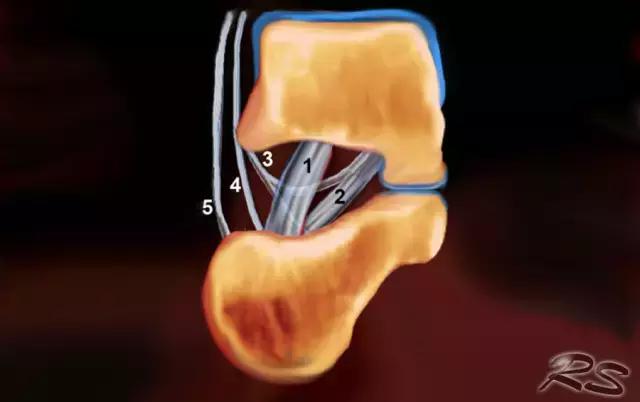

跗骨窦

跗骨窦是锥形空腔,在后内侧到前外侧方向上延伸。它位于距骨的颈部和跟骨的前上表面之间的脚的外侧面。跗骨窦内侧继续作为跗管,这是距骨与跟骨间一个漏斗形的空间。它包含脂肪,动脉吻合,关节囊,神经末梢和五个韧带结构 - 下伸肌视网膜的内侧,中间和侧根; 颈韧带; 和骨间骨骨膜韧带(图)。

超声引导的跗骨窦的注射在右手侧与外侧入路。探头保持在冠状倾斜平面中。针沿着探头的长轴引入。

使用超声波可以容易地观察窦性骨壁。患者转向对侧,将待治疗的足以其内侧表面靠在桌面上,脚的外侧位于最上面。探头保持在关于脚的冠状平面中。

在跗骨窦被识别为跟骨的前处理和距骨颈之间的三角空间。针(箭头)的前端的锥形跗骨窦,这是由距骨(T)和跟骨(C)的边界内可以看到。